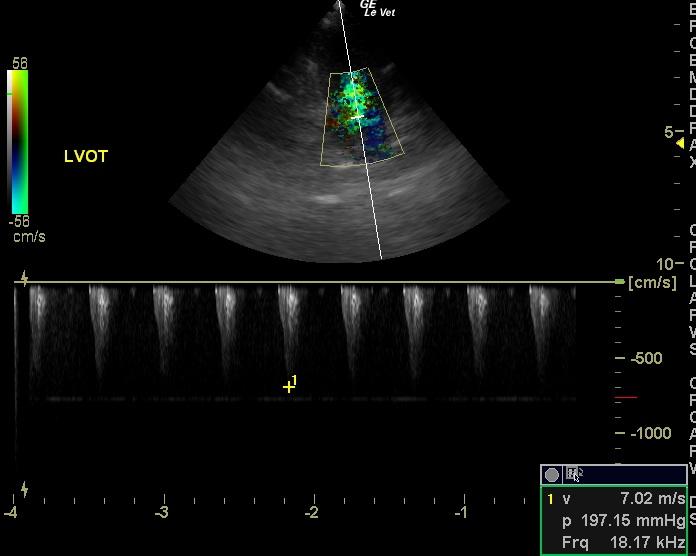

A 1-year-old intact male DSH was presented for anorexia over a 1-2 day period. Abnormalities on physical examination included hypothermia, a grade IV/VI systolic murmur, and ataxia. Leukocytosis was present on CBC. On survey radiographs, the intestines appeared to be bunched.